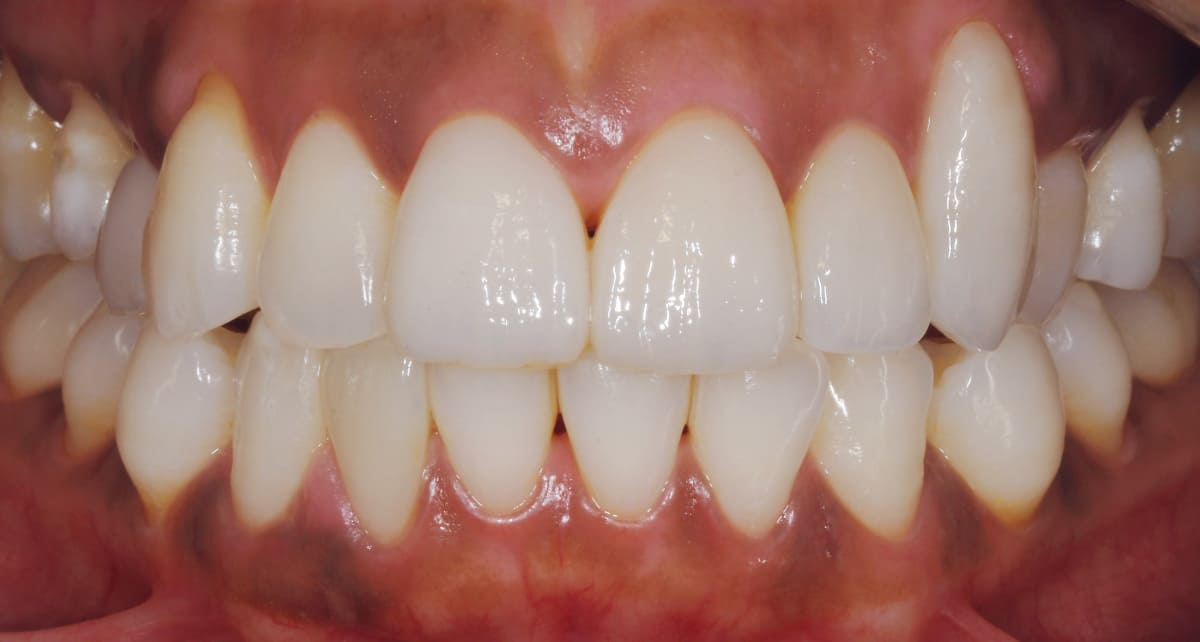

ジルコニア|ダイヤモンド並みに硬くカラダへの馴染みがいい。

Before

After

セラミックの一種のジルコニアで作った被せ物(クラウン)を使った治療。ジルコニアは人工ダイヤモンドと呼ばれるほどの硬度があるので奥歯にも適していてカラダには馴染みがいい素材。ただし透明感はセラミックより出しにくい。

【料金】10万円〜

【治療期間】1週間〜3週間程度

(特別な機材がある病院ではワンデイ治療が可能)